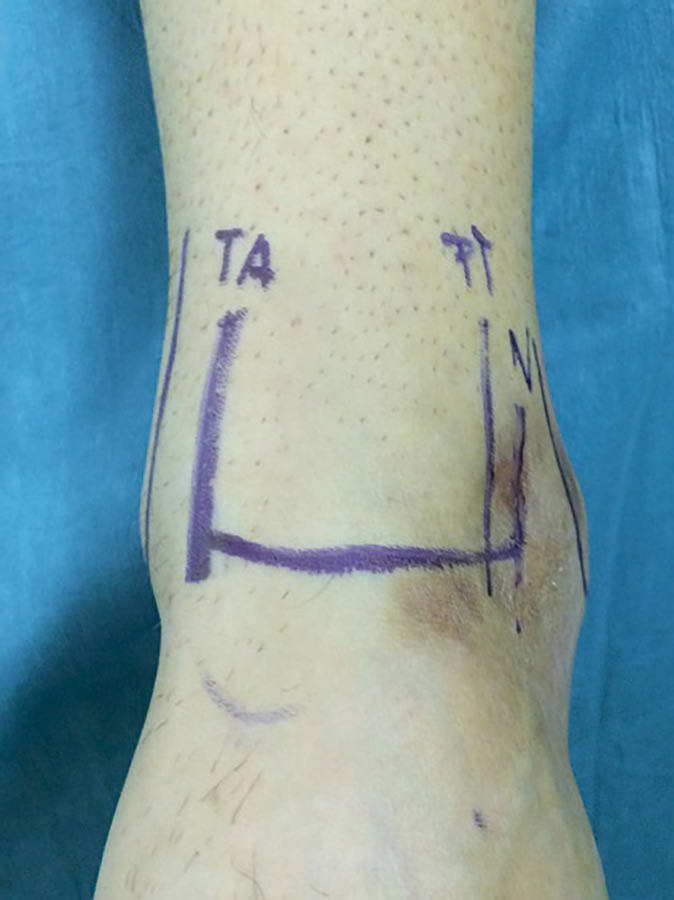

Una vez colocado en la posición anteriormente descrita, marcamos todas las estructuras anatómicas (maléolos, nervio peroneo superficial, tendón peroneus tertius/extensor del 5.º dedo y tendón tibial anterior) que nos permitirán realizar los portales minimizando el riesgo de lesionar estructuras neurovasculares y tendinosas(10)(Figura 2).

Figura 2. Marcaje de la anatomía del aspecto anterior del tobillo, para protección de la misma y facilitar el trabajo.